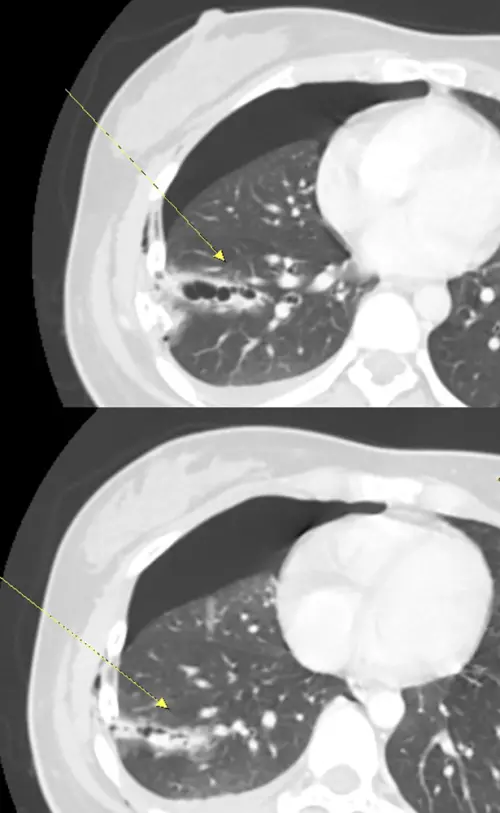

▲醫學影像檢查圖,兩節斷裂肋骨插入肺組織,造成肺臟破裂。(圖/澄清醫院提供) 胸腔損傷最怕「溫水煮青蛙」:血越積越多

胸腔外科杜承哲主任表示,胸腔損傷最怕的就是「溫水煮青蛙」,外觀看似只有瘀青,內部卻在持續出血。該患者經電腦斷層掃描,影像證實右側第5至7肋骨骨折,其中兩節肋骨明顯插入肺組織,造成肺臟破裂。